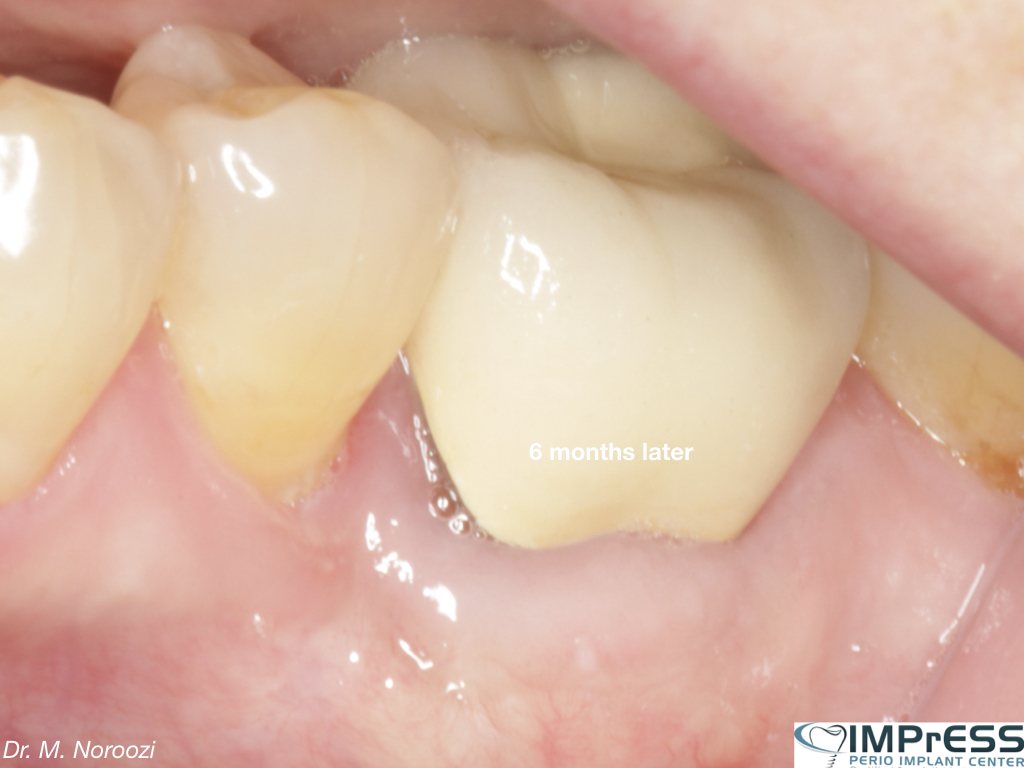

Immediate Implant Placement in Molar Extraction Site

immediate implant placement in molar site Dr. Noroozi